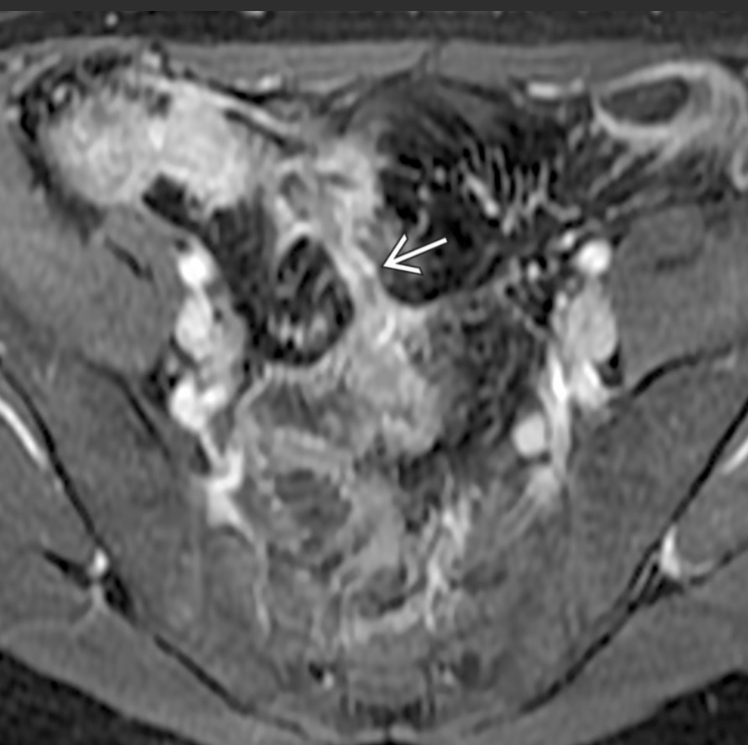

Abdome: cólon e reto

A __________ (doença de Crohn/retocolite ulcerativa) envolve todas as camadas intestinais, podendo resultar em fístulas.

A __________(doença de Crohn/retocolite ulcerativa) tem inflamação confinada à mucosa e submucosa do intestino grosso.

A

Doença de Crohn; retocolite ulcerativa.

Fístula entre alças de intestino delgado em paciente com Crohn; a alta resolução de partes moles da RM ajuda a delimitar melhor fístulas pequenas.